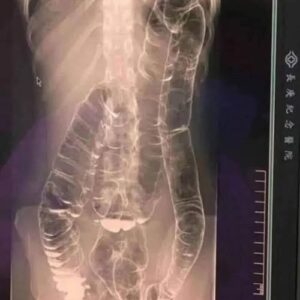

A saturated colon: when the body sounds the alarm

Constipation can feel trivial—until it turns terrifying. For one young woman, ignoring the warning signs led to a dangerously swollen colon and a race against time. The…